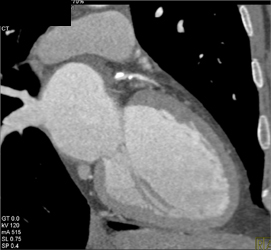

Diagnosis

Diseased LAD